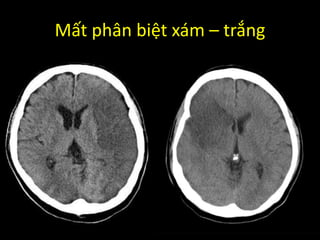

Mất phân biệt xám – trắng

Mất phân biệtxám – trắng

• #64 Phù não ở chất xám xảy ra nhiều hơn chất trắng do nhu cầu biến dưỡng ở đây cao hơn.

• #68 Do vùng chất xám bị phù não nhiều hơn dẫn đến đậm độ giảm xuống làm khó phân biệt giữa chất xám và chất trắng.

• #69 Phù não ở chất xám xảy ra nhiều hơn chất trắng do nhu cầu biến dưỡng ở đây cao hơn.